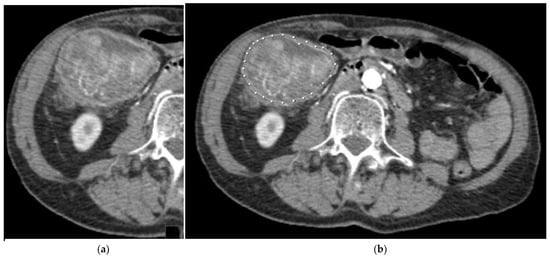

2.3. Segmentation